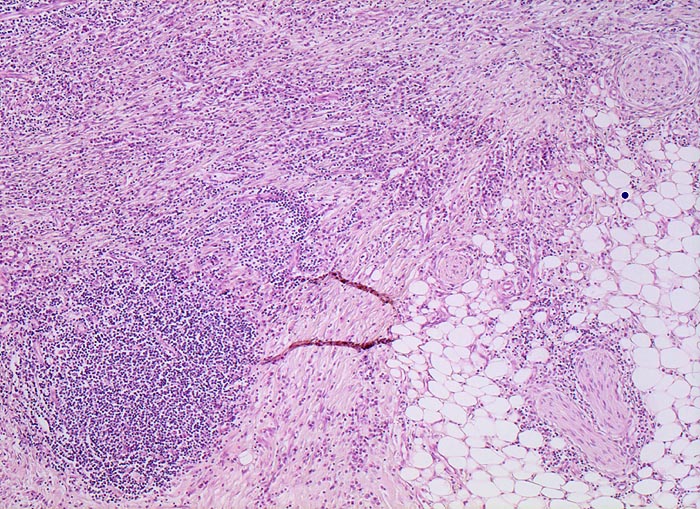

PathoPic ID 5084 - Morbus Crohn

Morbus Crohn

Entzündung / Reparatur

Ileum terminal

Darm, Anus

Fibrose und Entzündung des mesenterialen Fettgewebes mit

Lymphfollikelbildung. Auffallende Vermehrung kleiner

Nervenäste.

Bekannter Morbus Crohn. Resektion des terminalen Ileum wegen mechanischem Subileus und enterokutaner Fistelbildung.

Die Vermehrung von Nerven ist typisch bei Morbus Crohn.

Histologie

50